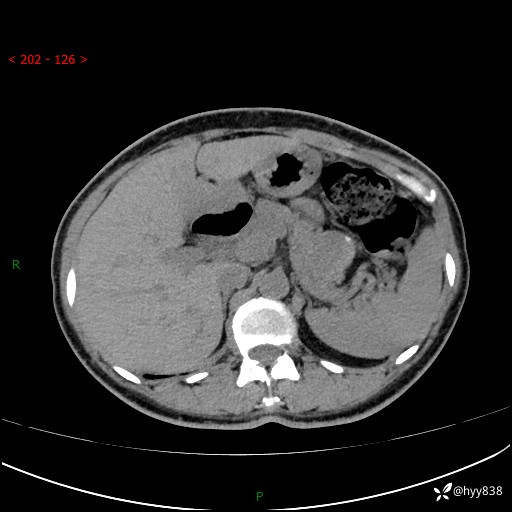

增强动脉期+静脉期

img